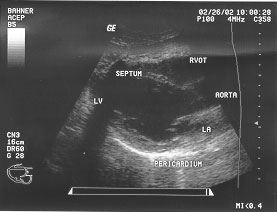

Cardiac - long parasternal (labeled)